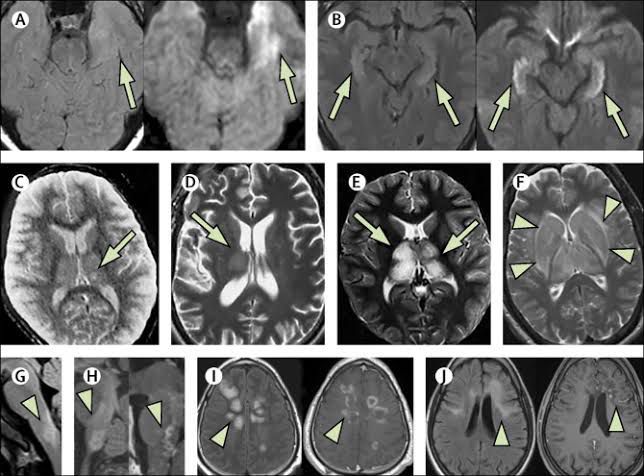

Encephalitis is inflammation of the active tissues of the brain caused by an infection or an autoimmune response. The inflammation causes the brain to swell, which can lead to headache, stiff neck, sensitivity to light, mental confusion and seizures.